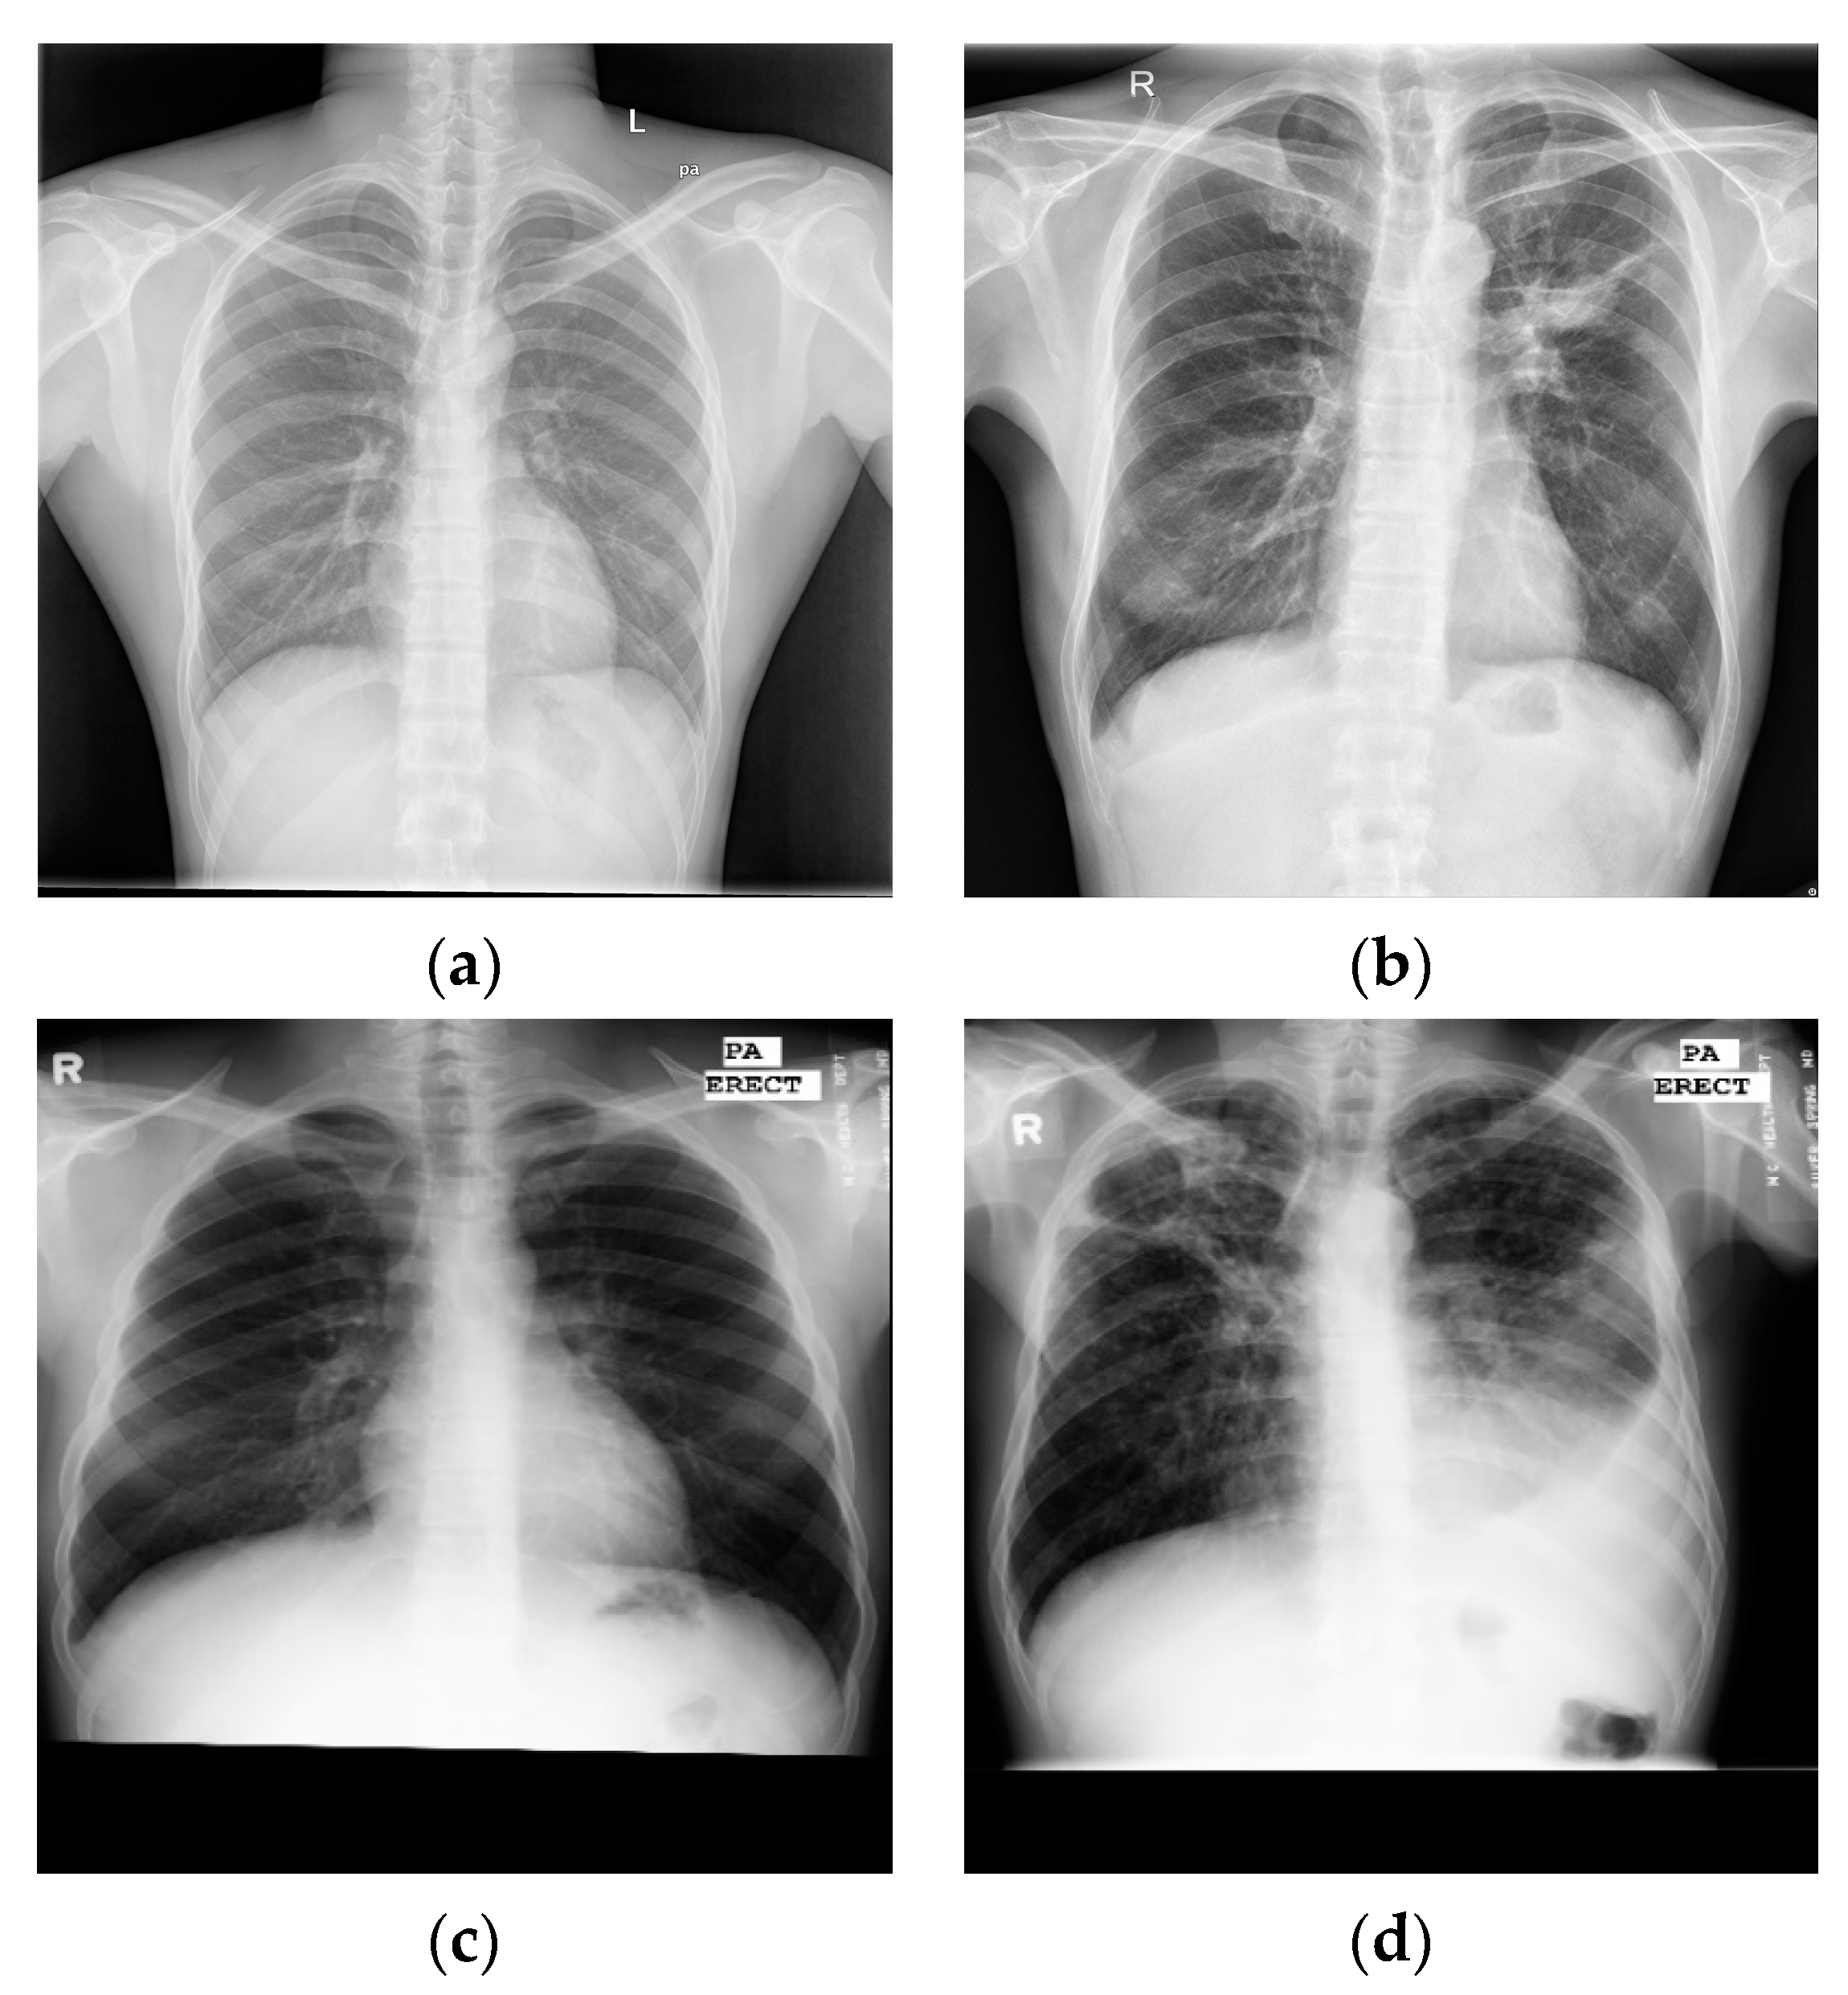

Through the above research, analysis, and related experiments, it was found that, firstly, the effect of the lung segmentation algorithm on chest X-ray images is affected by the different imaging manifestations of tuberculosis. Figure 1 shows four X-ray images of TB patients, and the marked areas in Figure 1a,b are the lesions. The segmentation of lung parenchyma leads to the omission of some focal points. In Figure 1c,d, the ribs and lesions in the marked area partially coincide. If rib suppression or lung parenchyma segmentation is performed, the focus will be hidden. After the chest X-ray images of the above four types of tuberculosis are segmented, some of the lesions are missing, resulting in poor performance in CNN classification. Secondly, the classic classification deep CNNs (VGGNet [8], DenseNet [9], etc.) and variant networks similar to them have excellent performance, but they are difficult to deploy on devices with low hardware, due to the amount of model parameters, computational complexity, and weights.

Figure 1.

Chest X-ray images of individual tuberculosis patients: (a) consolidation of the upper lobe of the right lung with cavities; (b) tuberculous exudative pleurisy; (c) secondary tuberculosis of right upper lung; (d) consolidation of right hilar with enlarged lymph nodes.